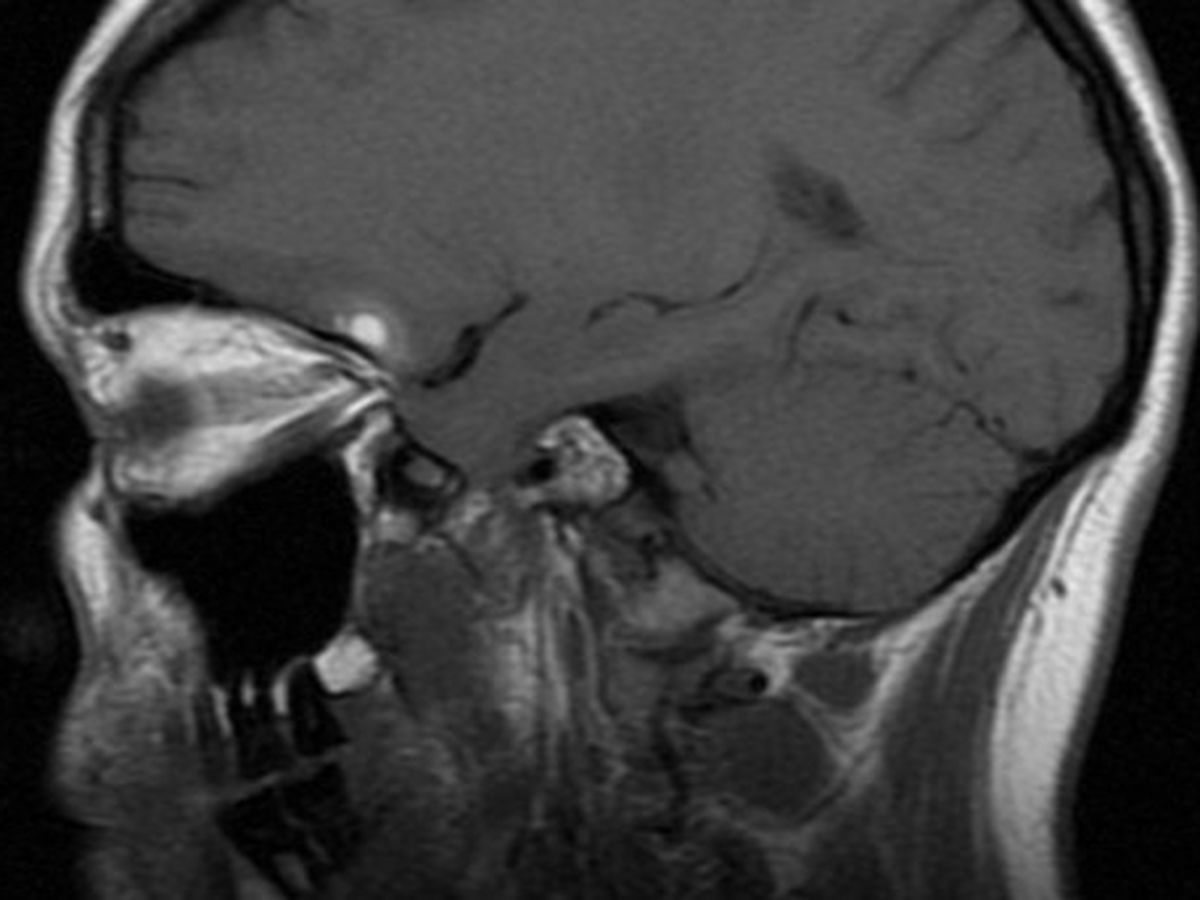

Join our campaign to help our friend, Emily DeCola! Not long ago, Emily was struck by a cyclist while crossing 2nd Ave. on her way to work. As her head hit the pavement, her marvelous grey matter jostled around, causing some brain bruising, a small hematoma, and injuring the delicate nerve between her nose and noggin, ending her sense of smell.Without a sense of smell, her sense of taste and her enjoyment of life have been flattened to a dull Salty, Bitter, Sweet, Sour experience of the world.